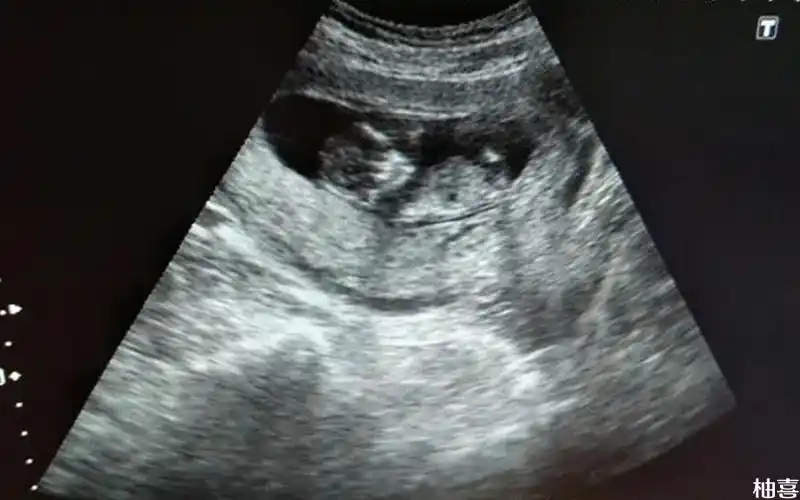

孕12周胎儿头臀径为55是生男孩还是女孩几率大